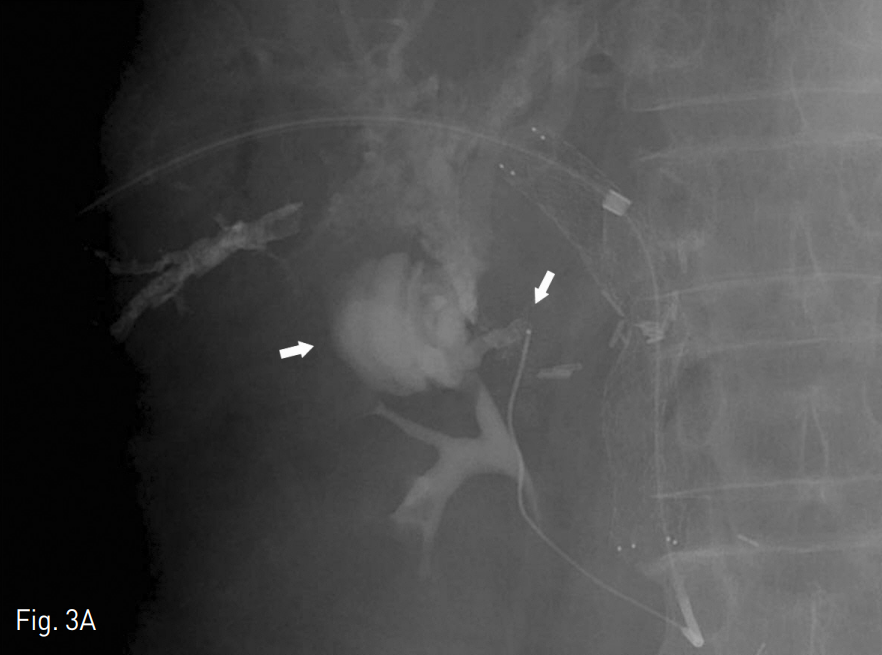

Fig. 3

A. Second transhepatic portogram with microcatheter shows active contrast media leakage to jejunum (arrows)

B. Seletive embolization with microcoils and recanalization with balloon dilation and stent placement were performed and portogram shows some residual cavernous transformation and patent portal vein flow.